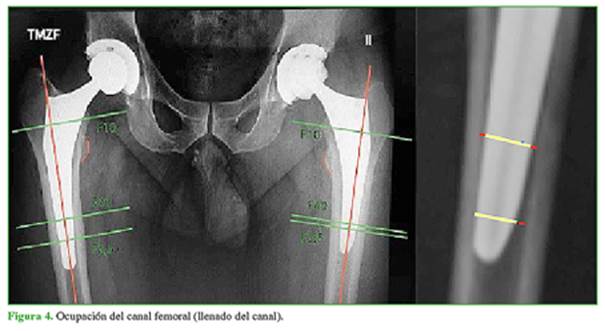

El porcentaje de ocupación del canal femoral por parte del implante en el plano coronal (llenado del canal) se evaluó en tres zonas (medición del ancho del implante dividido el ancho del canal femoral): proximal a 10 mm por encima del trocánter menor (FP), medial a 60 mm por debajo del trocánter menor (F60) y distal a 2,5 mm proximal a la punta del tallo femoral (F2,5) (Figura 4).